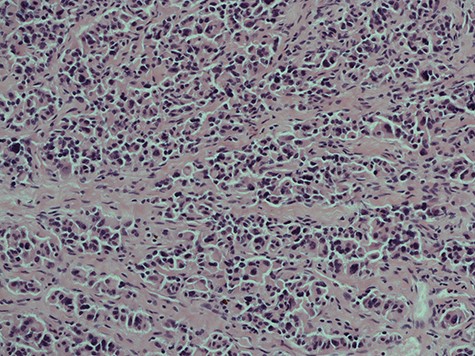

Initial examination showed soft, non-tender abdomen. Rectal examination revealed a suspicious anterior rectal mass. An urgent colonoscopy was therefore arranged and biopsies returned to show evidence of ulcerative colitis (UC) but no masses/neoplasia. Despite establishing the diagnosis and initiating appropriate Asacol and mesalazine treatment, she subsequently became significantly unwell and presented through the emergency department with severe abdominal pain, distention and vomiting. Physical examination revealed a blood pressure of 101/67 mmHg, HR of 123 beats/min, respiration rate of 24 breaths/min and saturations of 90% in room air. Computed tomography (CT) abdomen and pelvis not only showed descending colon inflammation and severe terminal ileitis but also moderate volumes of free fluid with extensive intra-abdominal inflammation. Initial laboratory blood tests were Hb 132, WBC 8.23, Plts 44, lactate 1.2, CRP 72, K+ 3.3, AST 46, Albumin 37. PR bleeding continued and haemoglobin levels began to drop out of proportion, reaching a low of 70 g/l as well as derangement of her coagulation studies. She was then escalated to critical care given her persistent hypotension and DIC, but ultimately she underwent emergency laparotomy. In theatre, we identified a massive retroperitoneal haematoma and approximately 30 cm of gangrenous terminal ileum. Patchy gangrene tissue of the ascending and descending colon was noted with preservation of the sigmoid colon. A subtotal colectomy was performed with end ileostomy and the cross-stapled sigmoid stump was left in situ. Additionally, two large (3 cm) abnormal mesenteric lymph nodes were also identified adjacent to the DJ flexure. These were resected for histological analysis. Histology of the lymph node surprisingly showed evidence of metastatic neuro-endocrine carcinoma with characteristics of solid trabecular growth and moderate nuclear pleomorphism (Figs 3 and 4). Post-operatively, she underwent a number of investigations in hope to identify the primary, as well as tests to identify the cause of the thrombosis.

Histological slice of the specimen acquired on the second lymph node removal.

A histological slice of the resected second lymph node tumour; viewed under x20 power.